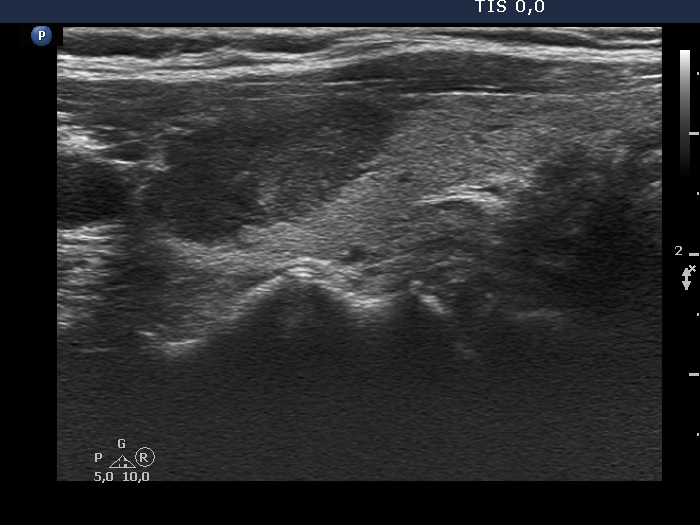

Ultrasonography. The thyroid was echonormal. There were several nodules in the left lobe. The largest in the upper pole presented all but one of the possible suspicious characteristics, it was deeply hypoechoic, had irregular margins, a microcalcification and showed abutting and bulging contours. Moreover, the intranodular vascularization was irregularly increased. One of the other lesions presented back wall figures while the third one showed taller-than-wide shape.